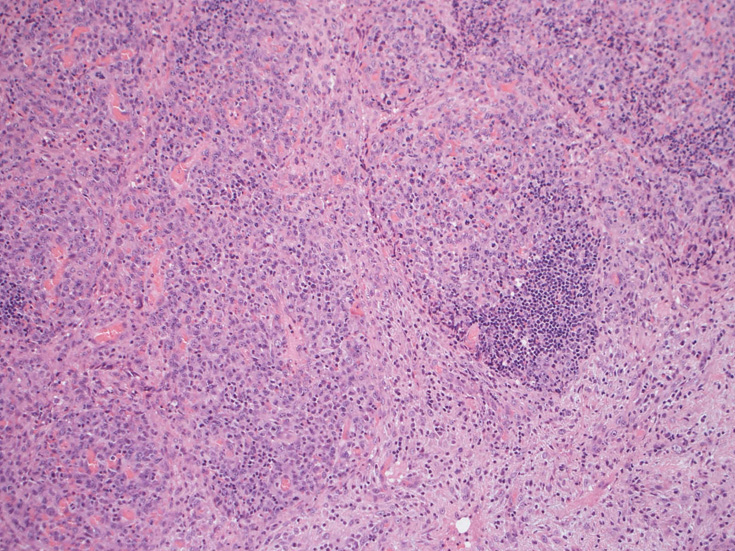

リンパ節, 増殖腫瘍細胞の病理所見

腹膜脂肪組織内から生検されたリンパ節は基本構造を失っている。低倍率のHE所見では異型細胞が不鮮明な結節構造を形成して増殖している。一次リンパ濾胞を腫瘍細胞が置換しているように見える所見がある。

高倍率x400では, 増殖細胞はcentroblastに似て複数の明瞭な核小体をもった淡明な大型類円ないし卵円形核を持っている。核分裂像が多い。この症例では多型はめだたない。典型的な腎臓型のくびれた核を持つ細胞などはない。ALKの形態的variant症例と考えられるが, 化学療法後の再発による影響も否定できない。

CD30はほぼ全ての腫瘍細胞に陽性となる。膜とゴルジ装置が染まり, 図のように細胞質内に斑点状の染まりが認められます。増殖細胞はCD3, CD20陰性.

この症例では多くの腫瘍細胞がCD5陽性となり、CD30と同じ染色パターンを呈した。